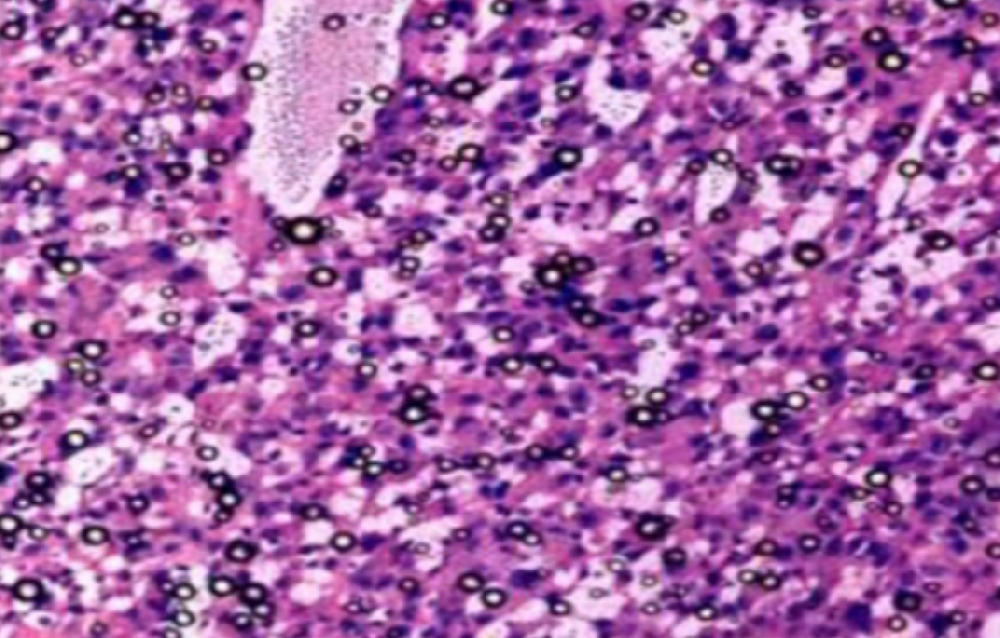

切片质量参差不齐?我们总结了15个HE染色常见问题及解决方法

HE染色,全称苏木精-伊红染色法(Hematoxylin and Eosin staining),是最常见的组织切片染色技术之一,用于在显微镜下观察和分析组织或细胞的结构和形态。虽然HE染色是最常···